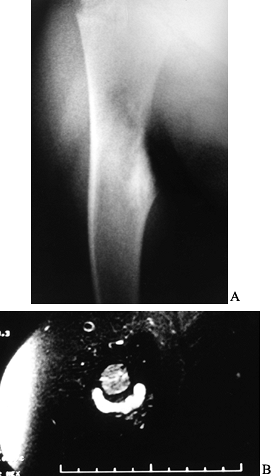

![]() |

|

Figure 127.1. AP radiograph (A)

of the tibia in a patient with osteoid osteoma. Note that the nidus is not well visualized although there is thick, mature periosteal elevation and some medullary reactive bone in the lateral aspect of the proximal tibial metaphysis. The sagittal (B) and axial (C) MRI show extensive marrow edema and soft-tissue edema surrounding the proximal tibia. The edema extends well beyond the lesion. The nidus is visualized as a low signal (dark area) in the midst of the bright edema, which is present both in the soft tissues and in the medullary cavity. A CT scan (D) more clearly shows the radiodense nidus in the lateral aspect of the tibia. In this case, the nidus is in the medullary cavity and the thickness of the cortex is readily apparent. There is also thickening of the trabecular bone surrounding the lesion. The adjacent fibula is normal, and the soft tissues do not appear abnormal as they did on the MRI. The portable scanner used for intraoperative bone scans (E) allows precise intraoperative imaging of the area of abnormality and helps to plan the surgical approach. Disappearance of the area of increased uptake following excision of the nidus helps to confirm that it has been completely excised. |

Important aspects of the preoperative management include planning the

most appropriate surgical approach, selecting a method for

intraoperative localization of the nidus, and determining if a less

invasive method is a reasonable alternative to wide excision. A CT scan

is often useful in helping to plan the most direct operative approach.

The method by which intraoperative localization of the nidus is to be

accomplished must be determined prior to surgery. Intraoperative bone

scintigraphy, tetracycline labeling, CT guidance, and conventional

radiography have all been used (85,155).

Intraoperative nuclear scanning takes advantage of the lesion’s ability

to concentrate radioisotopes following preoperative administration. The

area in question is sequentially scanned intraoperatively until

activity is appreciably diminished (Fig. 127.1E) (85). This indicates that the lesion has been completely removed.